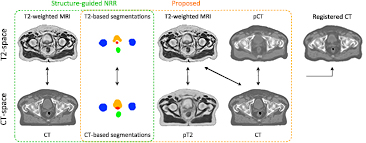

After generating the pCT and pT2, we improved the CT to T2 registration by registering the set {T2, T2seg, pCT} with the set {pT2, CTseg, CT}, using the LNCC between imaging channels and the KLD between segmentation channels. Note that the similarity term between the T2 and CT channels was preserved to account for multi-modal correlation terms. The non-rigid registrations were performed with a pyramidal approach with three levels. The finer lattice of control points had a spacing of 7.5 mm along each axis. The new coordinate mapping between CT and T2 was used to update the CT alignment to the T2 space. The images used as inputs to align for each atlas the CT and T2-weighted MR images, and create the initial and refined atlas databases are displayed in figure 2.

Figure 2. Inputs of the multi-channel registration used to align for each atlas the CT and T2-weighted MR images, and create the initial (green) and refined (orange) atlas database. Note that the pseudo CT (pCT) was generated from the T2-weighted MR image and the pseudo T2 (pT2) from the CT image.

Standard image High-resolution imageThe refined multi-atlas database consisted for each atlas of a T2-weighted MR image, a T2-based segmented image, a T1-weighted MR image and a CT image, all co-registered. The number of atlases was artificially increased by left-right flipping the images.